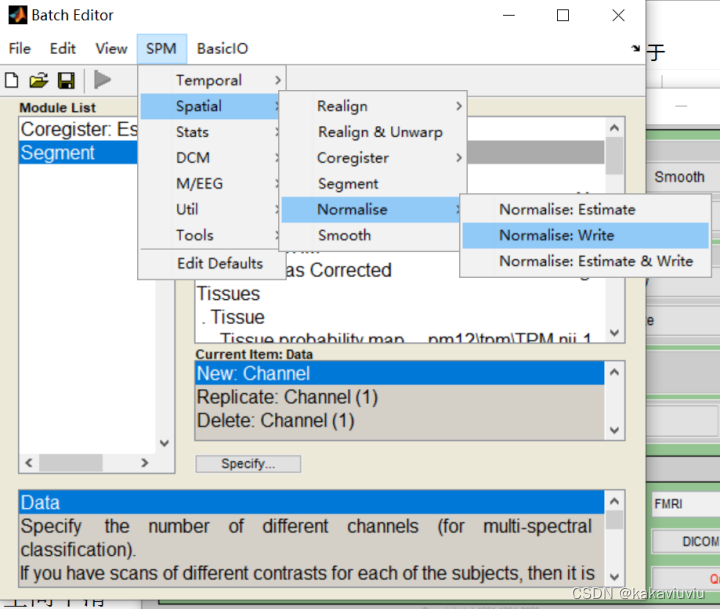

再选择normalise

修改boundingbox和体素3 3 3